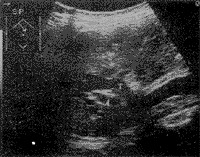

肿瘤部位胆管壁全层受侵,浆膜面欠清,门脉(PV)管壁受压变形(↑),超声诊断为PV(+),手术发现门脉被周围浸润组织包裹,无法切除。

图2 肝门部胆管癌(T)